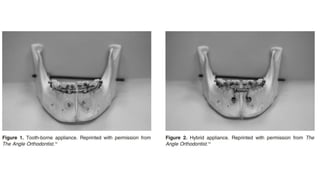

Tooth Borne

+Razdolsky’s tooth borne

ROD Appliance

+ Guerrero’s et al intraoral

distractor (Hybrid)

+ Hyrax (SARME)

Razdolsky’s toothborne ROD Appliance intraoral

distractor

Hyrax

Guerrero’s et al intraoral distractor

It is attached superiorly to teeth by orthodontic bands and

inferiorly to bone by bendable forked arms.